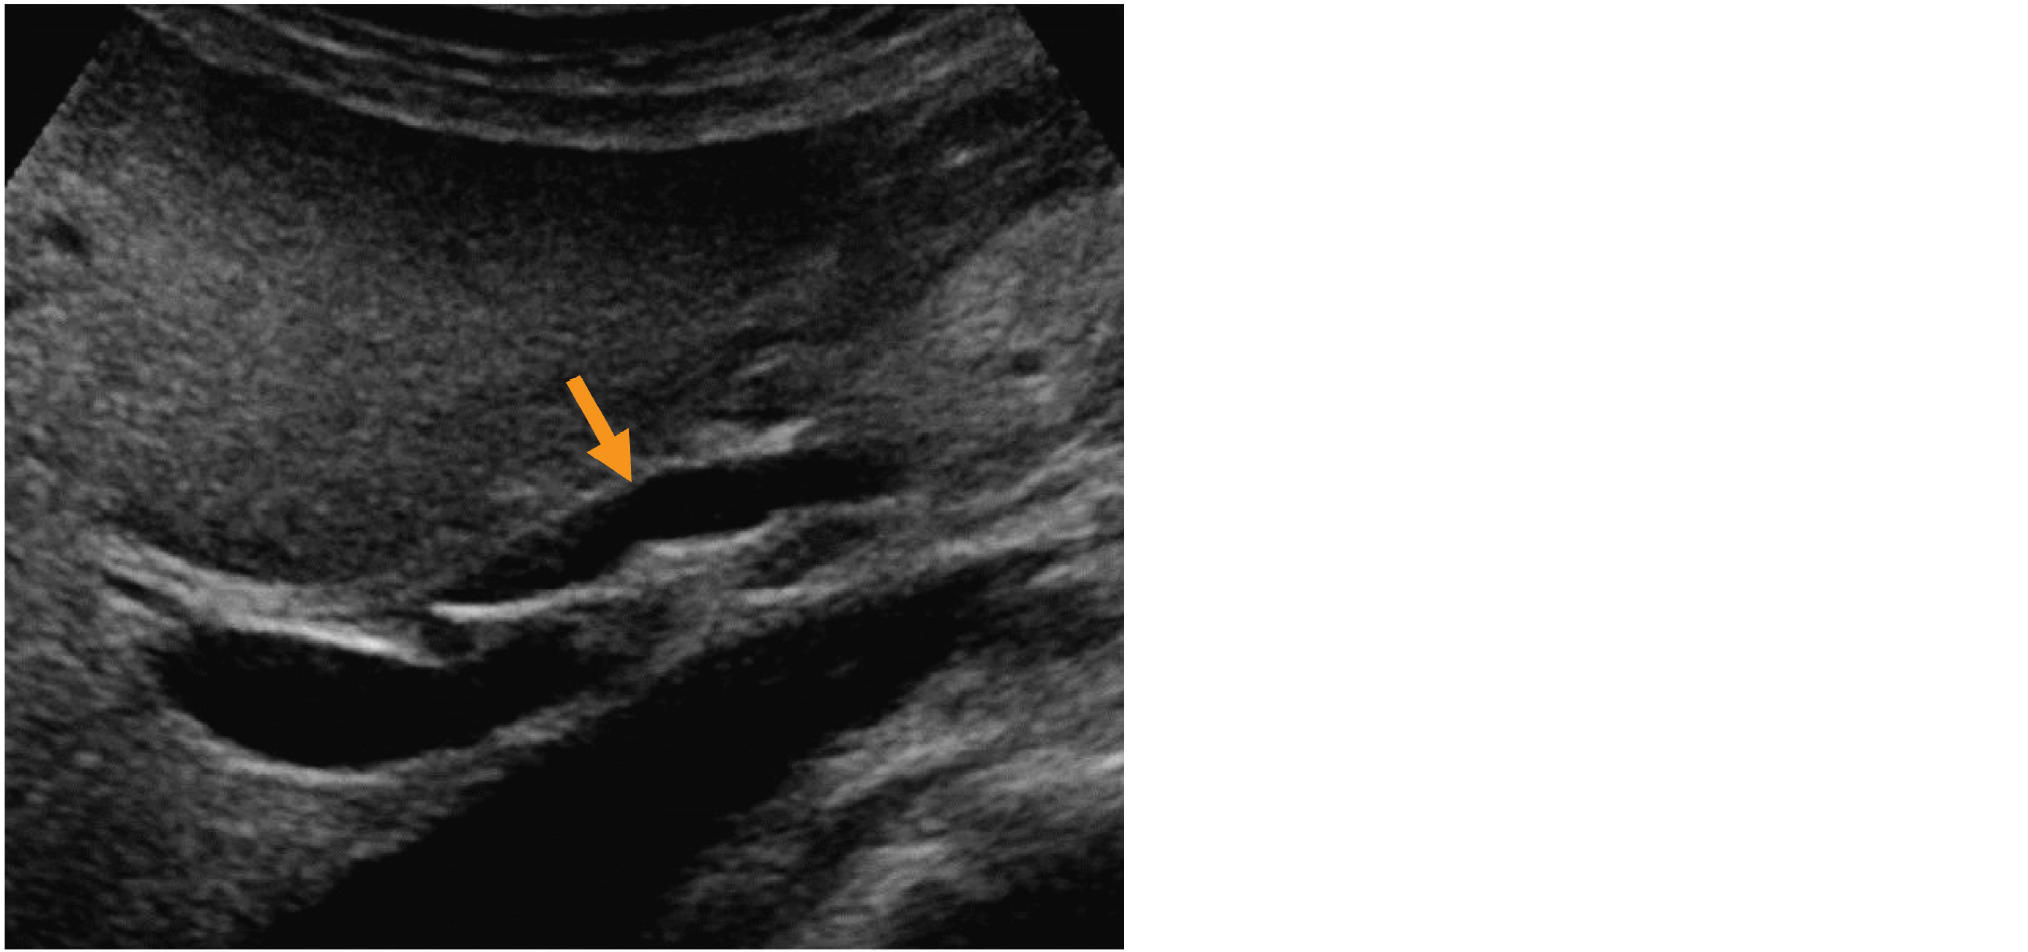

右上腹部走査による超音波B モード像を示す。

矢印で示すのはどれか。

• 1. 門 脈

• 2. 肝静脈

• 3. 肝動脈

• 4. 主膵管

• 5. 総胆管